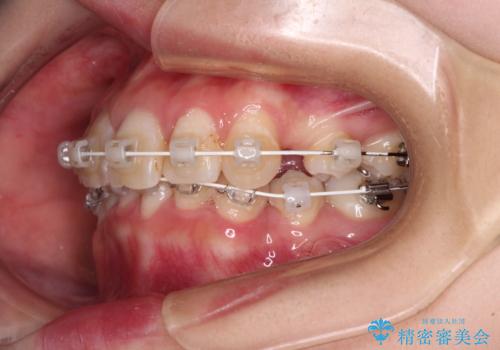

デコボコと深い咬み合わせ ワイヤー装置での抜歯矯正

- 矯正装置

- 審美装置

咬み合わせが深く、そのままでは上顎の抜歯スペースが閉じきらない可能性があったため、治療初期から深い咬み合わせを改善させるように試みました。

実際にはなかなか改善されず、当初予定よりも治療期間がやや長期化してしまいました。